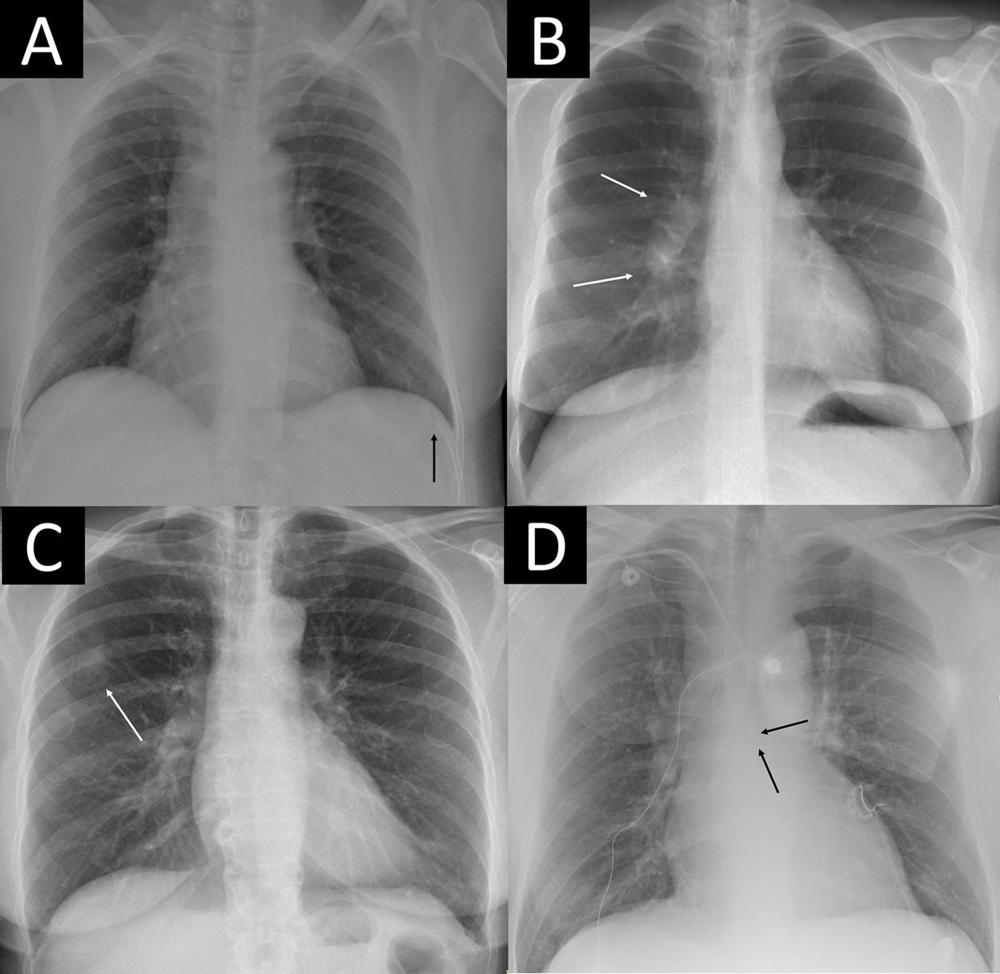

Figure 3. Four examples of remarkable chest X-rays with missed critical findings. The artificial intelligence (AI) tool was postprocessed by the AI vendor by scaling each of the 85 remarkable individual predictions to a normalized value and using the case-level highest of the scaled scores as the overall probability score from 0 to 1 for “remarkableness” (ie, the probability for abnormal or remarkable findings by the AI). (A) Chest X-ray in a 49-year-old female patient shows a slightly visible acute rib fracture (arrow) that was missed by the AI at all thresholds and also missed by the radiology report. (B) Chest X-ray in a 30-year-old female patient shows enlarged hilar lymph nodes (arrows) missed by the radiology report but not the AI at any threshold. (C) Chest X-ray in a 67-year-old female patient shows a tumor mimicking pleural plaque (arrow) that was reported in the radiology report (where the patient was referred for CT) and missed by the AI at the 98.0% threshold but not the 99.0% and 99.9% thresholds. (D) Chest X-ray in a 64-year-old male patient shows a central venous catheter possibly entering the azygos vein (arrows), which was classified as unremarkable in the radiology report. The AI missed the critical finding at the 98.0% threshold but not the 99.0% and 99.9% thresholds.